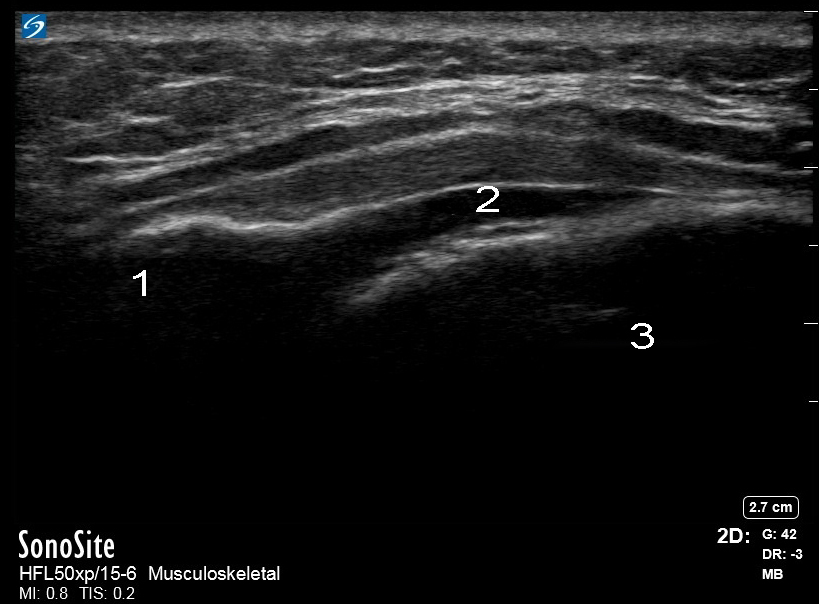

Image : Colonne : Ligament sacro-coccygien

Colonne : Anatomie caudale épidurale

1. Face postérieure

2. Hiatus

3. Face postérieure